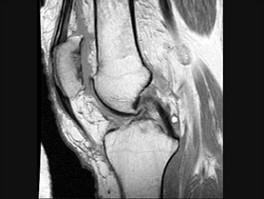

髌骨软骨软化症(如图)的治疗原则哪项是错误的 ( )A、非甾体类抗炎药B、一旦发现尽可能早手术治疗C、物理治疗D、关节内封闭 ...

问题 髌骨软骨软化症(如图)的治疗原则哪项是错误的 ( )

选项 A、非甾体类抗炎药 B、一旦发现尽可能早手术治疗 C、物理治疗 D、关节内封闭 E、股四头肌锻炼

答案 B